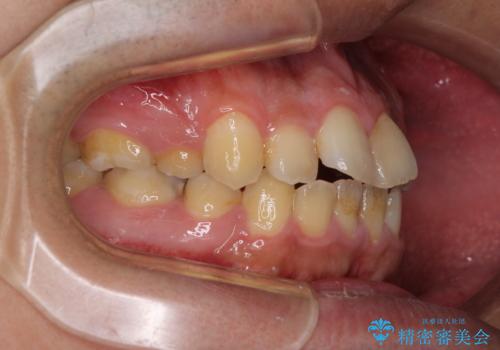

後戻りでデコボコの前歯 インビザライン矯正治療

下顎骨が左側に変位しているため、正中が合わないことは予想できましたが、歯列が整った後も咬み合わせが安定せず、咬み合わせを落ち着かせるために1年以上の期間を要しました。

噛みにくさの改善に時間がかかってしまうことがインビザラインの欠点の1つといえます。